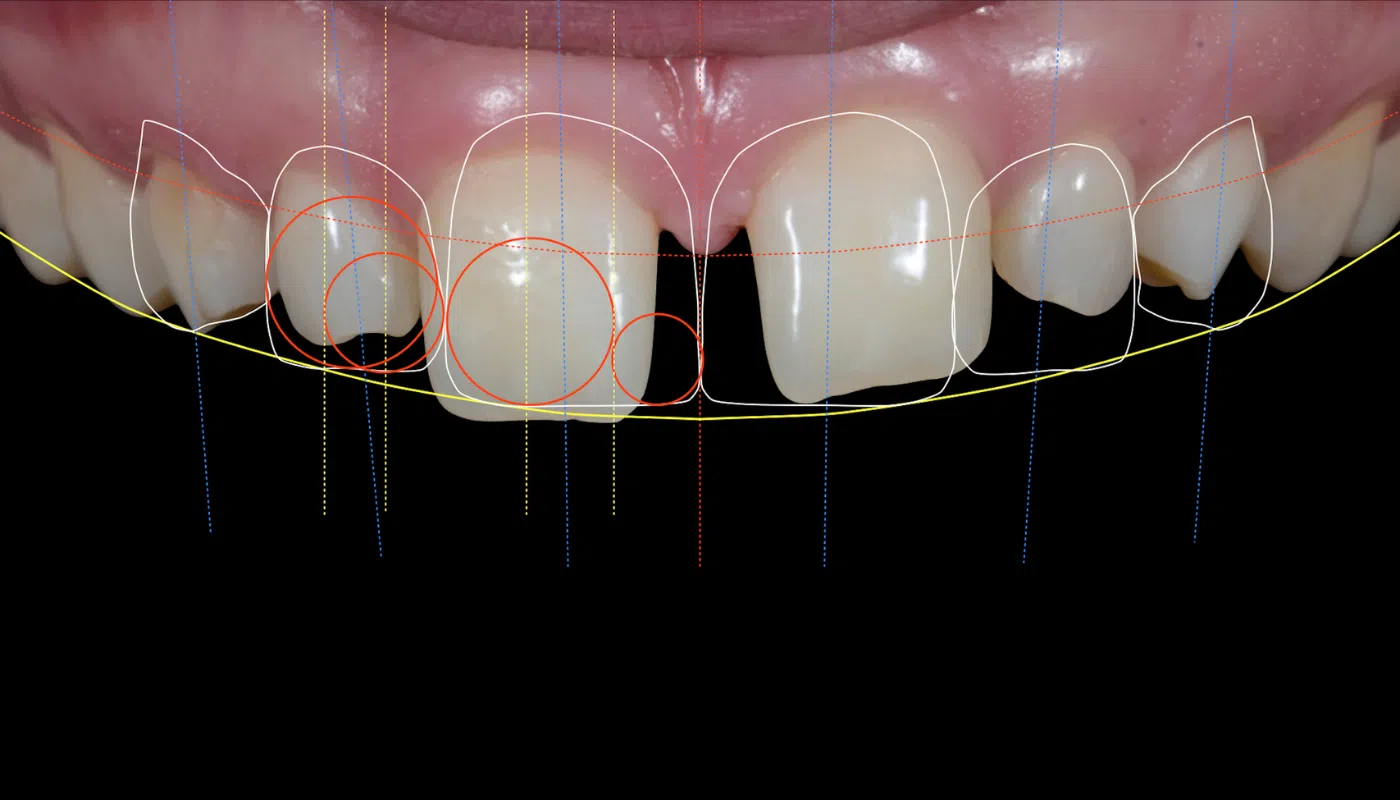

Smile makeover - Cost effective Smile improvement

At Lilladent, we offer a variety of minimal-invasive treatments to enhance both the function and aesthetics of your smile.